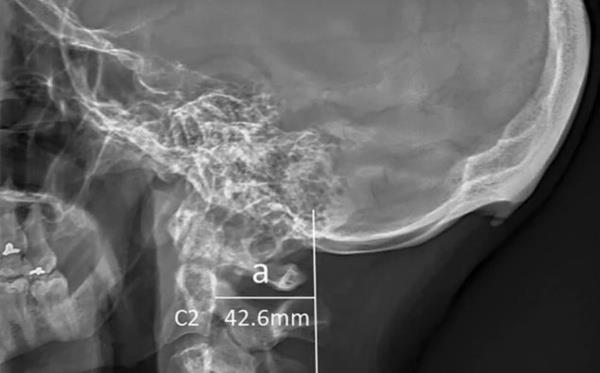

2. Avustralya’daki Sunshine Coast Üniversitesi’den bilim adamları Dr. David Shahar ve Prof. Mark Sayers, 18-30 yaş arasındaki 218 kişinin röntgen çekimlerini inceledi. Yapılan araştırmalar sonucu röntgen çekilen kişilerin neredeyse yarısının kafatası şeklinin yoğun cep telefonu ve tablet kullanımına bağlı olarak ‘değiştiği’, boynuzumsu bir çıkıntıya benzediği belirtildi.

Avustralya’daki Sunshine Coast Üniversitesi’den bilim adamları Dr. David Shahar ve Prof. Mark Sayers, 18-30 yaş arasındaki 218 kişinin röntgen çekimlerini inceledi. Yapılan araştırmalar sonucu röntgen çekilen kişilerin neredeyse yarısının kafatası şeklinin yoğun cep telefonu ve tablet kullanımına bağlı olarak ‘değiştiği’, boynuzumsu bir çıkıntıya benzediği belirtildi.

6. Ensenin üstünde sivrilen 10-30 milimetre arasında değişen çıkıntıya, &#8216;dış oksipital kabartı&#8217; deniyor. Dış oksipital kabartıya, taşınabilir dijital cihazlar yaygınlaşmaya başlamadan önce daha çok yaşlı insanlarda rastlandığı, gençlerde ise oldukça nadiren rastlandığı belirtiliyor.

Ensenin üstünde sivrilen 10-30 milimetre arasında değişen çıkıntıya, ‘dış oksipital kabartı’ deniyor. Dış oksipital kabartıya, taşınabilir dijital cihazlar yaygınlaşmaya başlamadan önce daha çok yaşlı insanlarda rastlandığı, gençlerde ise oldukça nadiren rastlandığı belirtiliyor.